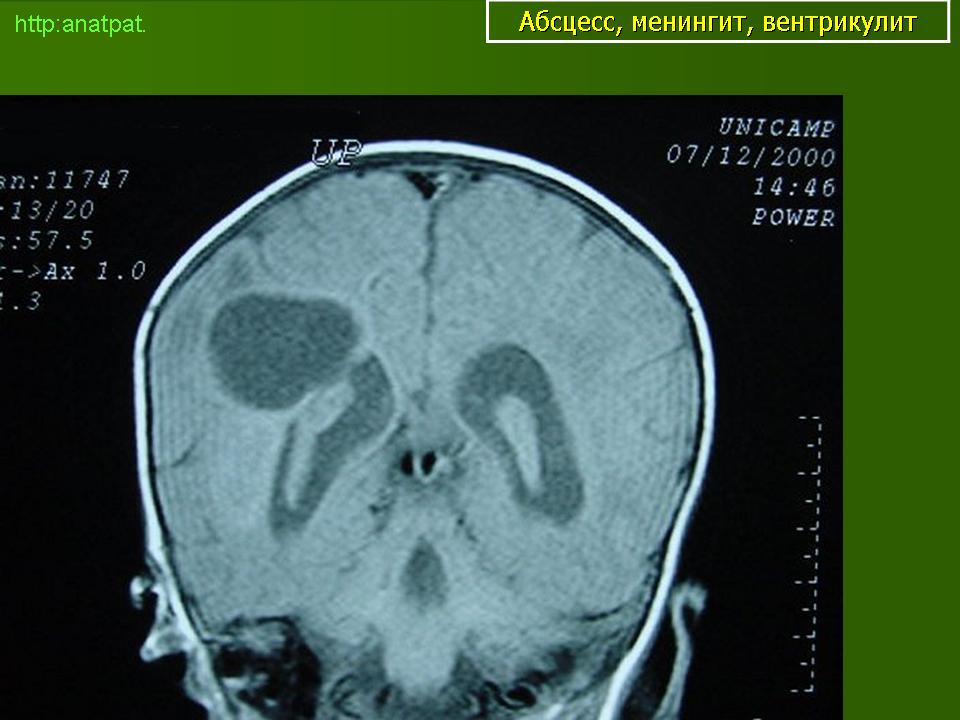

Абсцесс головного мозга – это очаговое скопление гноя в мозговом веществе, окруженное капсулой.

Абсцессы могут локализоваться в различных участках мозгового вещества. Обычно абсцессы сочетаются с менингоэнцефалитами, энцефалитами, сопровождаются повышением температуры тела, воспалительными изменениями крови и ликвора. Клиническая картина разнообразна и состоит из различных сочетаний общемозговых симптомов (головной боли, головокружения, тошноты, рвоты, нарушений сознания), менингеальной (оболочечной) и очаговой неврологической симптоматики.

Компьютерная (КТ) или магнитно-резонансная (МРТ) томография головного мозга являются ведущими методами диагностики посттравматических абсцессов, позволяющих судить об их расположении, объеме, структуре, консистенции, содержимом, воздействии на вещество головного мозга. Для исключения опухолей головного мозга, туберкулом, паразитарных заболеваний проводится ОФЭКТ (однофотонная эмиссионная компьютерная томография).